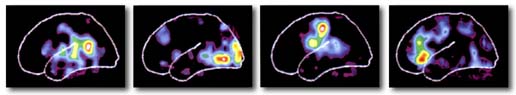

Por fortuna, hay una generación actual de científicos que ha incorporado la emoción y los sentimientos a su quehacer cotidiano y ya los estudian formalmente en el laboratorio. Contrariamente a lo que pudiera pensarse, no son los cardiólogos quienes pertenecen a esa generación, pues aunque se trate de asuntos que comúnmente el hombre ha depositado en el corazón, son más bien los neurólogos y otros neurocientíficos quienes desentrañan las complejidades biológicas de las emociones y los sentimientos. Lo hacen a sabiendas de que estos últimos son difíciles de estudiar porque son experiencias privadas. Las emociones, en cambio, por su carácter innato, tienen características públicas que las hacen accesibles al observador externo. Todo es que se tengan los medios adecuados que contesten puntualmente las preguntas y, como sucede a menudo en ciencia, se elija bien a los sujetos de estudio. Los medios ya existen y se perfeccionan continuamente; por ejemplo, los estudios radiológicos de imagen de altísima resolución capaces de ver el cerebro humano en tercera dimensión prácticamente como si estuviera abierto el cráneo. Otros no sólo lo ven, sino que muestran con colores las áreas del cerebro que una persona utiliza en determinado momento, por ejemplo, cuando siente tristeza o ira. Si estos instrumentos de investigación se aplican a personas sanas, el observador podrá entonces concluir el funcionamiento normal de esas zonas; pero si a quien se estudia es ahora un paciente con alguna lesión cerebral precisa que le ha producido cambios puntuales de conducta, por ejemplo falta de apego a las reglas sociales, o le ha causado incapacidad para reconocer y enfrentar el miedo, el investigador podrá cartografiar en el cerebro las zonas encargadas de regular esas funciones. Esto desde luego no quiere decir que el cerebro tenga partes dedicadas exclusivamente a reconocer o producir miedo, ira, tristeza, alegría u otras emociones primarias; sería ingenuo pensar que el tema es así de simple.